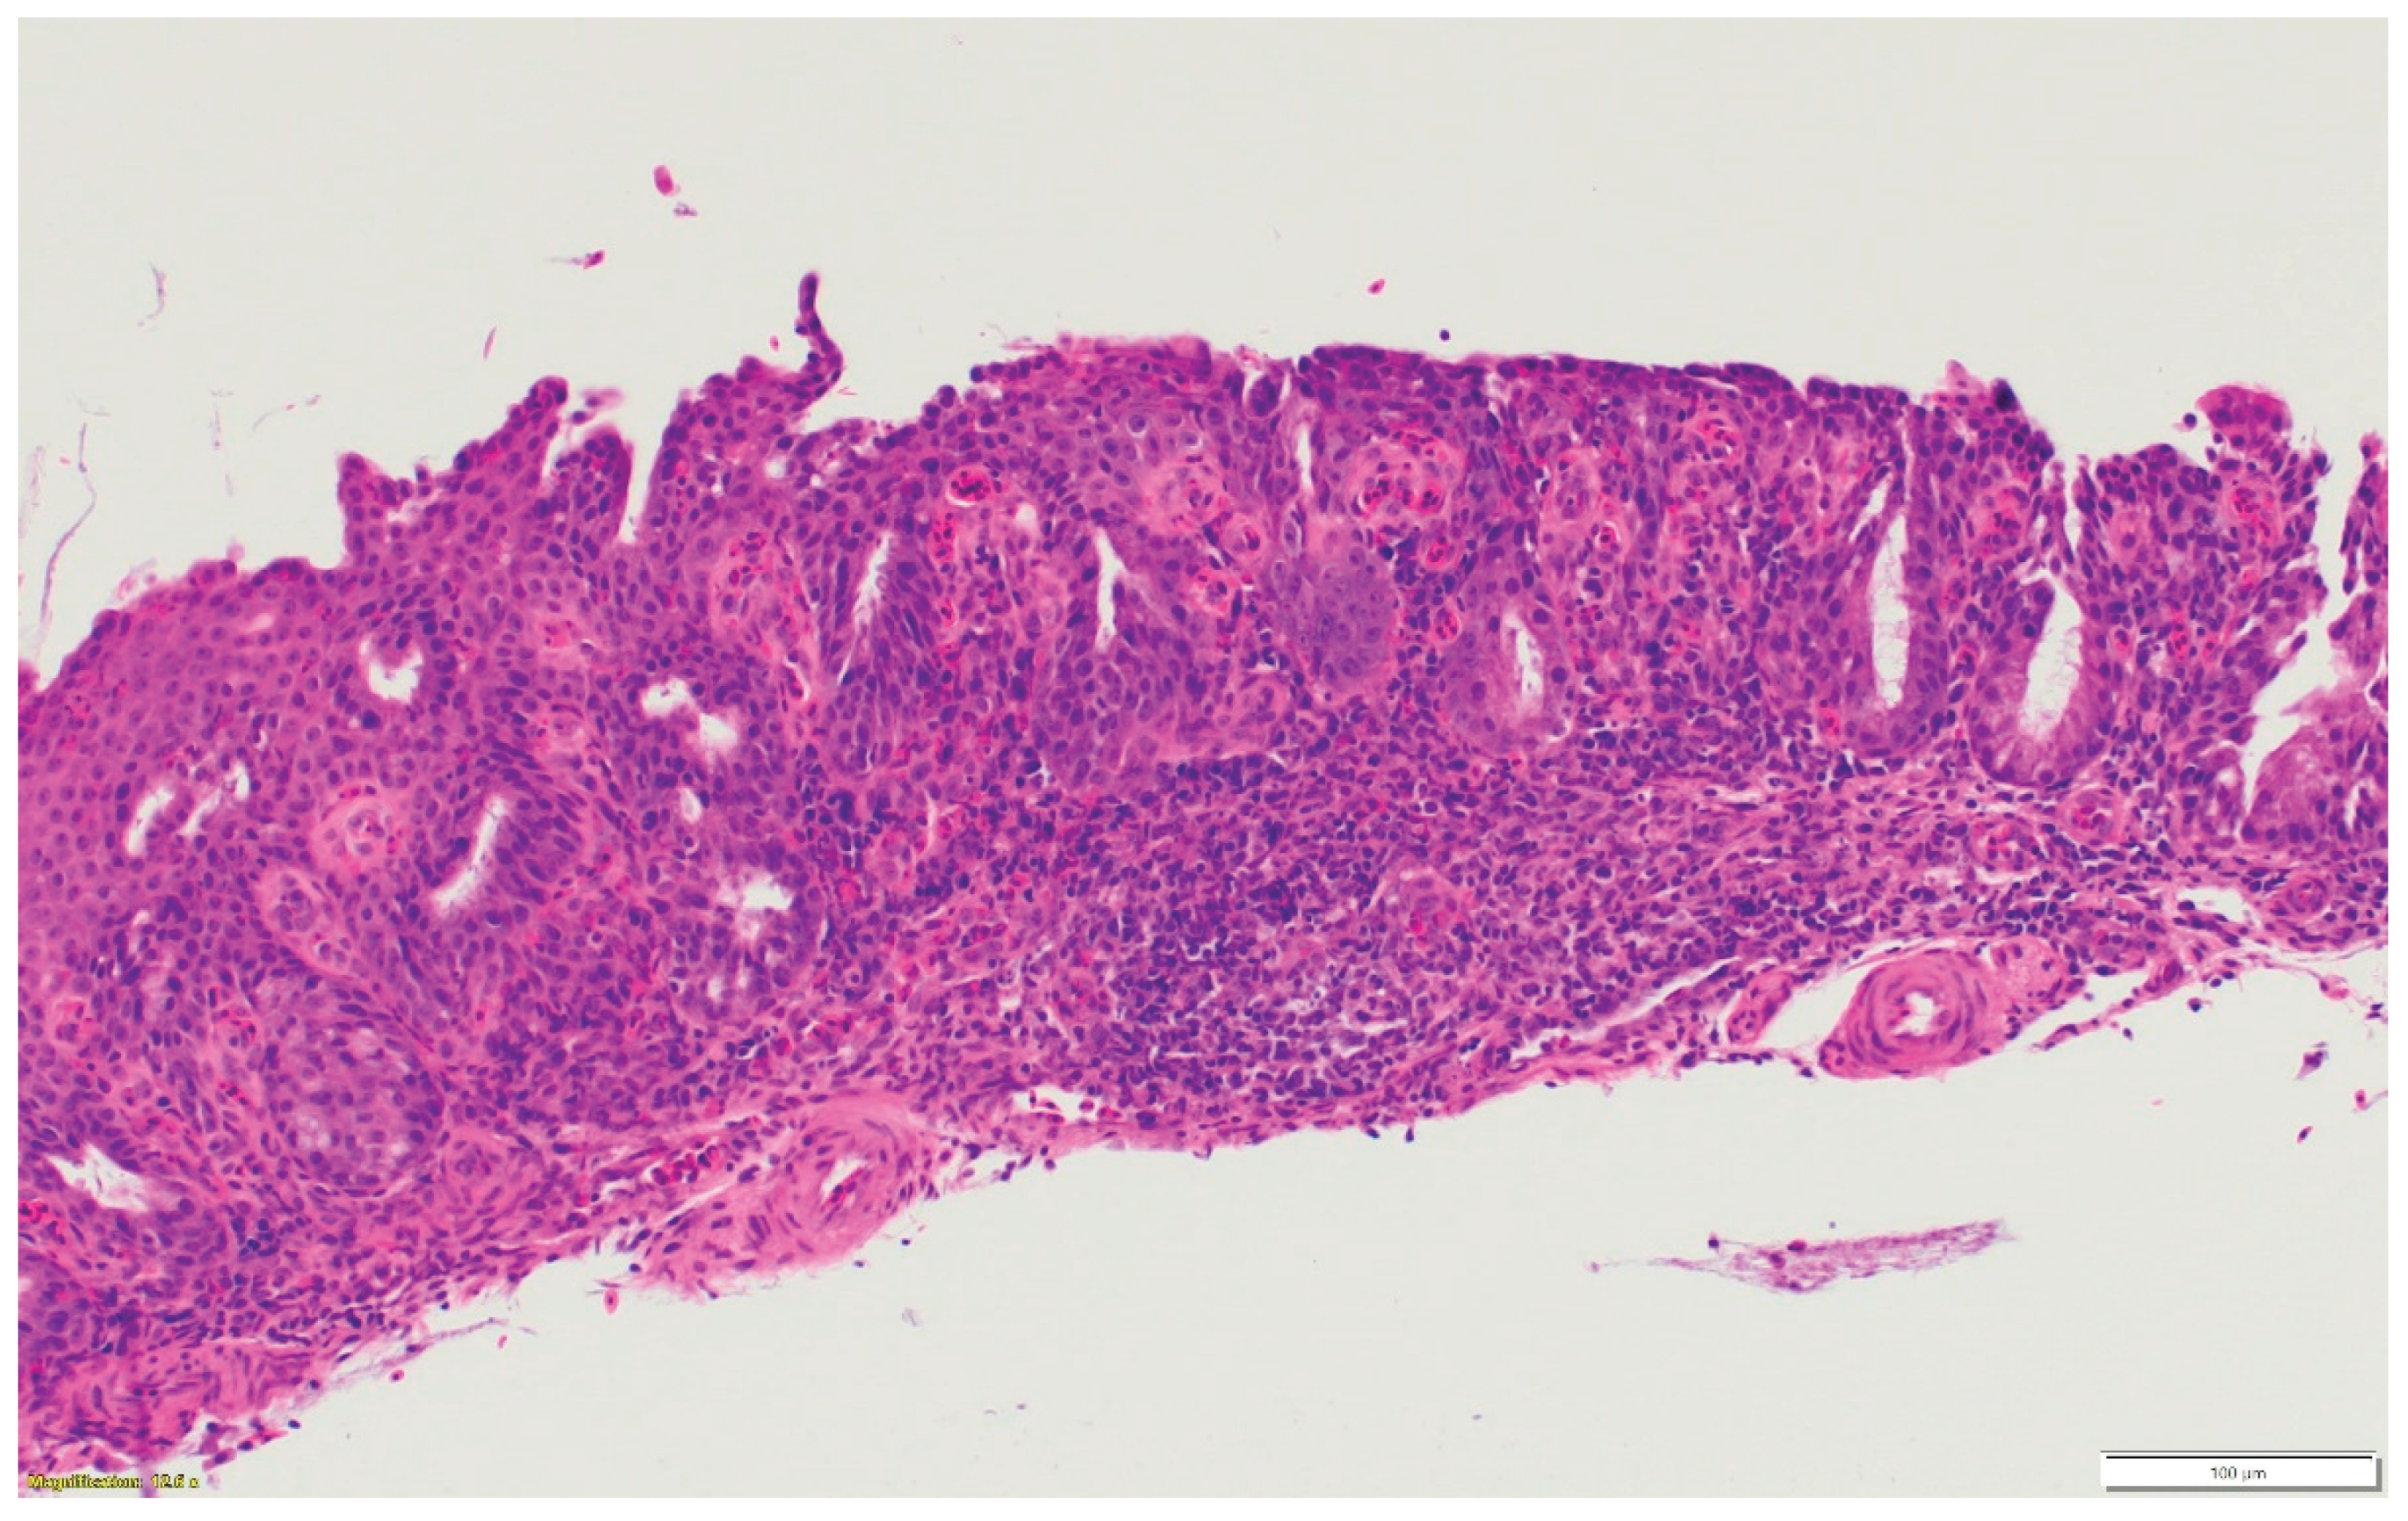

3.1. Turkeys infected with aMPV at 1-day-old (Figure 2a) had a higher total HRI compared with noninfected controls. The gap between the two groups increased significantly as the birds aged. Sinus and eyelid scores were the main contributors to the difference between the control and infected groups. A similar pattern was observed in groups inoculated at 7- and 14-day-old (Figure 2 b-c), but with higher scores. Sinus was the central part of the score difference, followed by the eyelids.

3.2. Chickens infected with aMPV at 7- and 14-day-old (Figure 3a-b): A similar pattern to the turkeys inoculated with AMPV at 7- and 14-day-old. Similarly, sinuses and eyelids created the main difference between the control and infected groups.

3.3. Turkeys inoculated with aMPV at 7 days of age showed higher lesion scores at 10 DPI compared with the non-infected control group. Sinus and eyelids were the main organs scoring points compared with other organs (Figure 4a).

3.4. Turkeys inoculated with low pathogenic avian influenza (LPAI-H4N6) at 7 days of age had also increased histologic lesion scores at 7 DPI compared with the non-infected control group. Sinus, lungs, eyelids, and trachea were orderly contributing to a higher total HRI (Figure 4b).